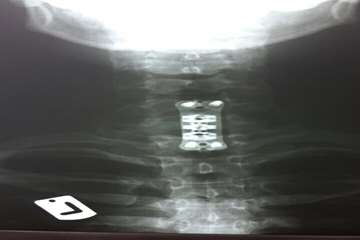

سپس برای حفظ پایداری ستون فقرات،بجای جسم مهره C7از مش کیج EXPANDABLE از جنس تیتانیوم استفاده شد.در نهایت یک PLATE بر روی مهره آسیب دیده قرار داده شده و با کمک 4 پیچ روی مهره بالا (C6) و مهره پایین (T1) فیکس شد.